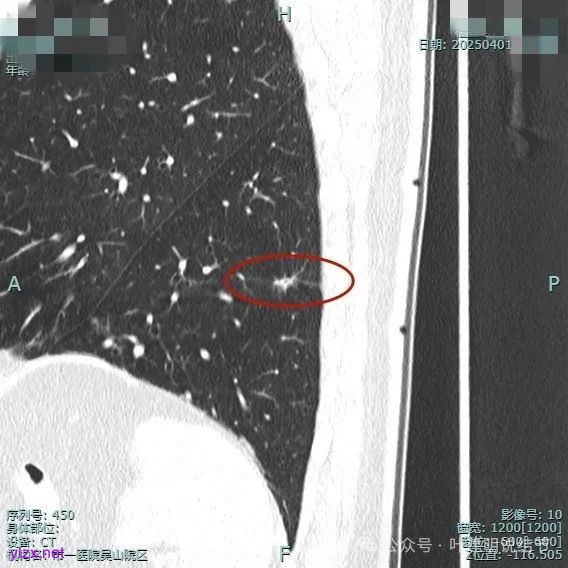

但纵向看是偏条状些的,密度较高,边上有少许磨玻璃成分,磨玻璃部分略显模糊。

整体纵向仍偏长条些,实性部分不太致密,边上磨玻璃成分的轮廓与界限不太清楚,毛刺显得长。

仍有支气管扩张,但较2024年时密度感觉低了点。

密度较淡且缺乏收缩力。

总体较之前密度有减低,缺乏聚拢性。